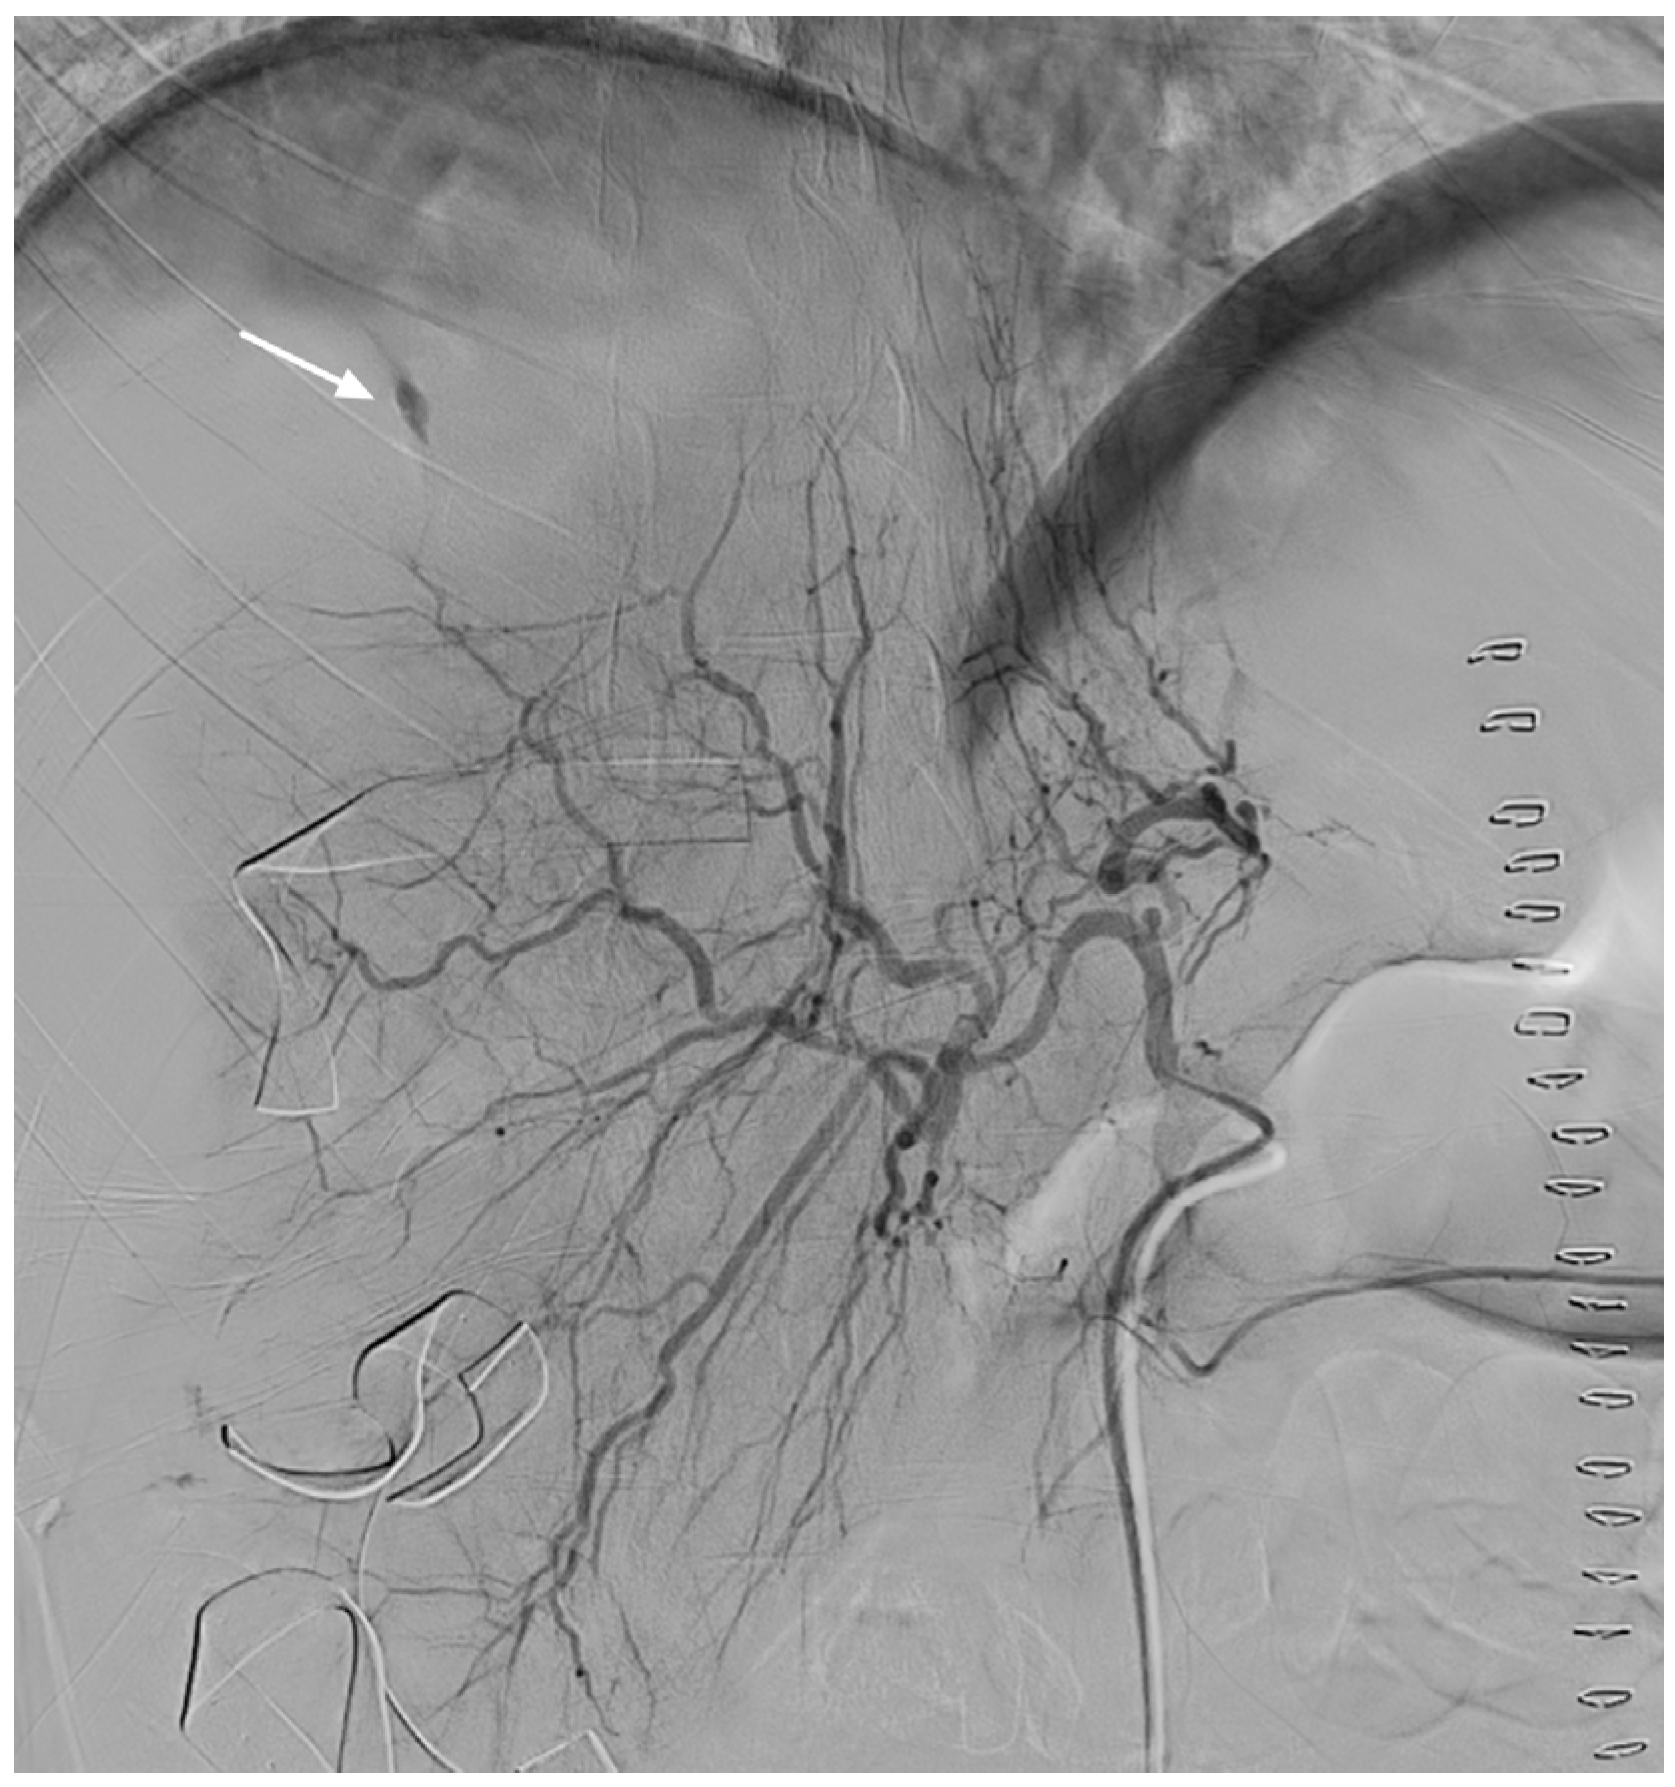

Transcatheter Arterial Embolization for Spontaneous Hepatic Rupture Associated with HELLP Syndrome: A Case Report

2. Case Presentation